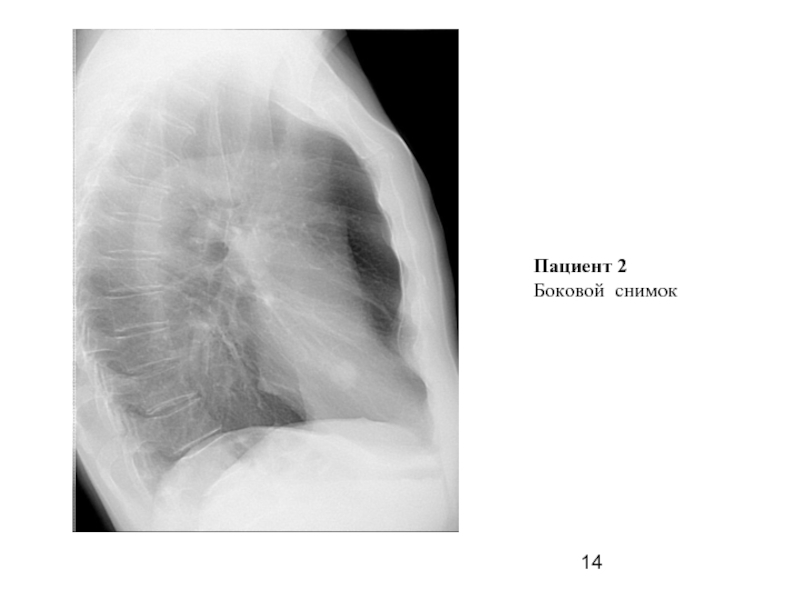

Слайд 14Пациент 2

Боковой снимок